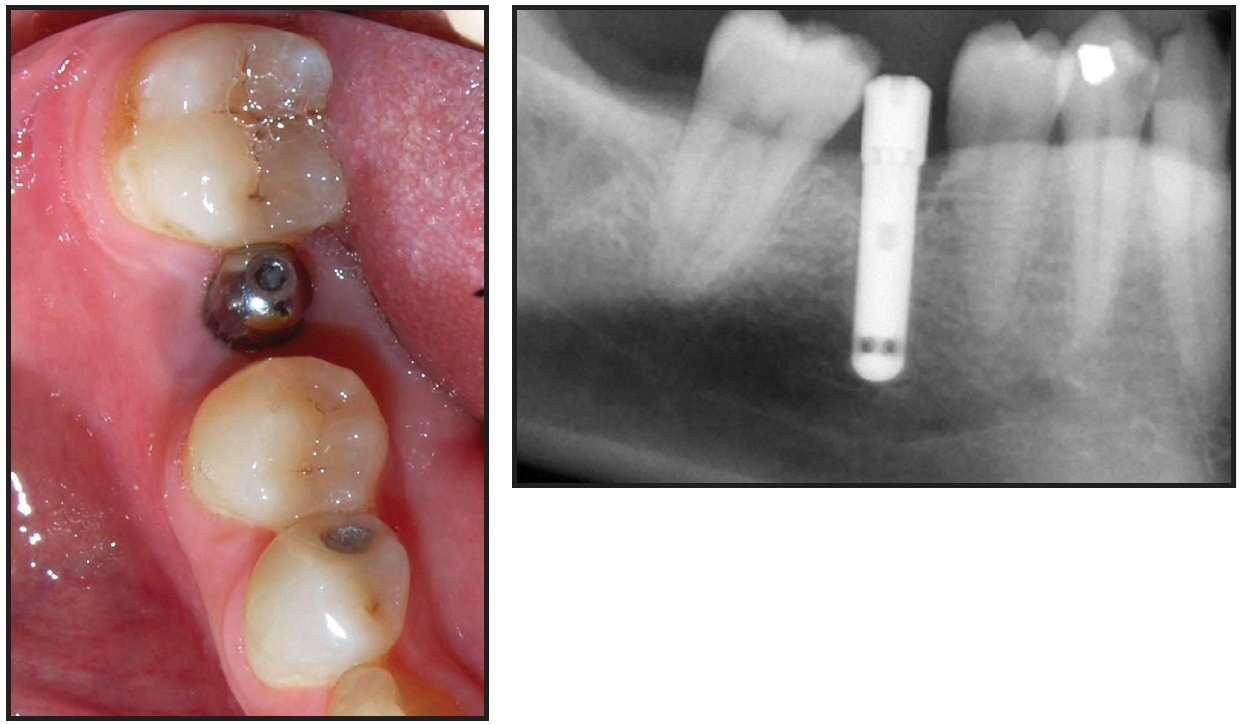

A 43-year-old male was evaluated for prosthodontic treatment of the left posterior dentition. The patient presented with a Class I mutilated occlusion, a supraerupted upper left second premolar, a missing upper left first molar, a failing mesio-occluso-distolingual amalgam on the lower left first molar, and a lingually displaced lower left second premolar with dental caries (Fig. 1).

Fig. 1 Case 1. 43-year-old male Class I patient with supraerupted upper left second premolar, missing upper left first molar, failing amalgam on lower left first molar, and lingually displaced lower left second premolar with dental caries.